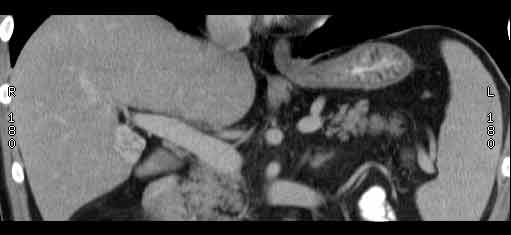

Сонограммы, КТ- артериальная, портальная и отсроченная паренхиматозная фазы

Сделали КТ (весьма похвальная тактика); по КТ: в артериальную фазу: периферическое усиление в виде сливающихся островков контраста, с центрипетальной направленностью. Венозная и отсроченная фаза-хорошее накопление контраста; образование практически изоденсно по отношению к паренхиме печени. Классика гемангиомы. Вуаля-диагноз на "тарелочке".